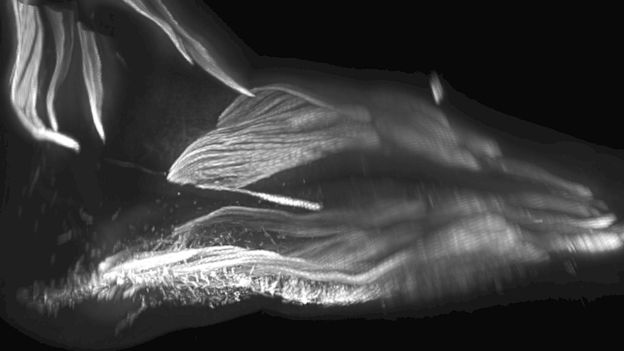

Bilim insanları bu bulguyu tespit etmek için 7-13 hafta arasındaki embriyo ve fetüsleri 3 boyutlu yazıcılarla inceledi.

Bebeklerin ayak kasları da icelendi.

Bilim insanları embriyoların ayaklarını gözlemlediğinde de bazı kasların önce oluşup sonra yok olduğunu keşfetmişlerdi.

Bu kaslar, maymunların ağaçlara tırmanmak ve nesneleri ayaklarıyla kontrol etmek için kullandığı kaslardı.